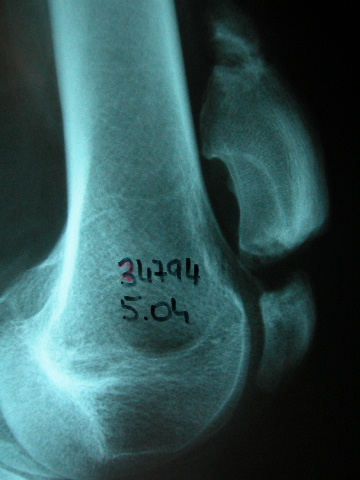

Prótesis completa de rodilla. Situación postquirúrgica. Lateral.

Prótesis completa de rodilla.Lateral.